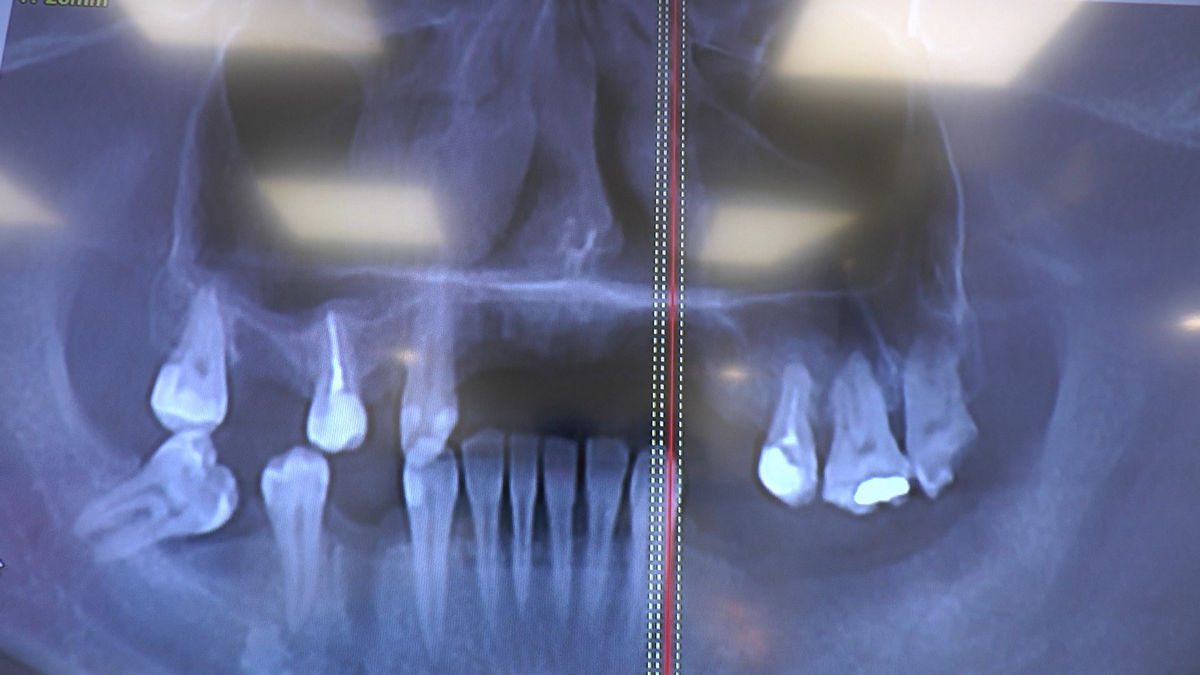

Practiculum Implantologii – Sezon V/B, sesja 8, część 4